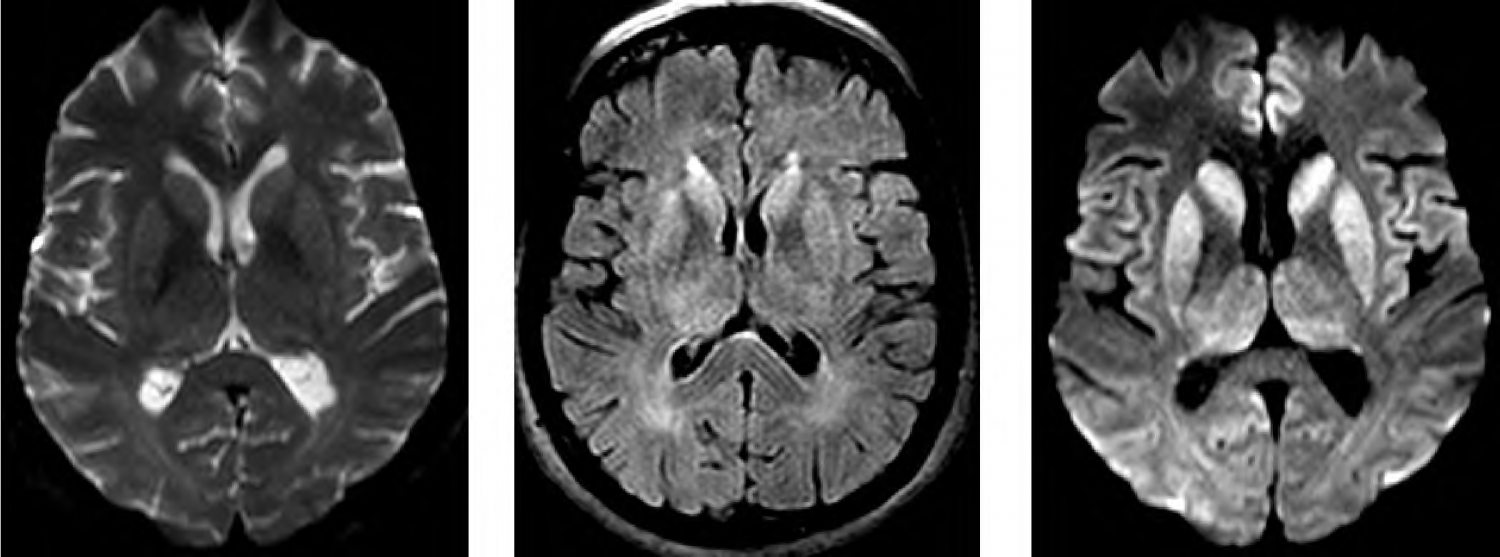

J.P, 58 anos, foi levado ao hospital com prejuízo cognitivo de início há 3 meses, com evolução progressiva, envolvendo atenção, praxia, planejamento, orientação temporoespacial, função executiva e memória. Realizado miniexame do estado mental com 12/30 pontos. Avaliação funcional evidenciou prejuízos significativos de atividades instrumentais e básicas de vida diária. A família relata que há 6 meses vem apresentando desequilíbrio e quedas frequentes. O exame neurológico revelou presença de mioclonias frente a estímulos sensoriais. Os exames de sangue gerais solicitados vieram dentro do padrão de normalidade, descartando infecções ou distúrbios hidroeletrolíticos. EEG demonstrou padrão periódico de ondas trifásicas sobre atividade de fundo atenuada. Realizou exame de ressonância de crânio (T2, FLAIR e DWI) que mostrou as seguintes imagens:

De acordo com a imagem apresentada no caso clínico, o principal achado que auxiliaria a confirmação diagnóstica é:

Atenção: Para responder às questões de números 39 a 41, considere o caso clínico abaixo.

J.P, 58 anos, foi levado ao hospital com prejuízo cognitivo de início há 3 meses, com evolução progressiva, envolvendo atenção, praxia, planejamento, orientação temporoespacial, função executiva e memória. Realizado miniexame do estado mental com 12/30 pontos. Avaliação funcional evidenciou prejuízos significativos de atividades instrumentais e básicas de vida diária. A família relata que há 6 meses vem apresentando desequilíbrio e quedas frequentes. O exame neurológico revelou presença de mioclonias frente a estímulos sensoriais. Os exames de sangue gerais solicitados vieram dentro do padrão de normalidade, descartando infecções ou distúrbios hidroeletrolíticos. EEG demonstrou padrão periódico de ondas trifásicas sobre atividade de fundo atenuada. Realizou exame de ressonância de crânio (T2, FLAIR e DWI) que mostrou as seguintes imagens:

No exame de líquor, o teste a ser pedido e que é um importante biomarcador para a confirmação diagnóstica é:

Atenção: Para responder às questões de números 39 a 41, considere o caso clínico abaixo.

J.P, 58 anos, foi levado ao hospital com prejuízo cognitivo de início há 3 meses, com evolução progressiva, envolvendo atenção, praxia, planejamento, orientação temporoespacial, função executiva e memória. Realizado miniexame do estado mental com 12/30 pontos. Avaliação funcional evidenciou prejuízos significativos de atividades instrumentais e básicas de vida diária. A família relata que há 6 meses vem apresentando desequilíbrio e quedas frequentes. O exame neurológico revelou presença de mioclonias frente a estímulos sensoriais. Os exames de sangue gerais solicitados vieram dentro do padrão de normalidade, descartando infecções ou distúrbios hidroeletrolíticos. EEG demonstrou padrão periódico de ondas trifásicas sobre atividade de fundo atenuada. Realizou exame de ressonância de crânio (T2, FLAIR e DWI) que mostrou as seguintes imagens:

O diagnóstico mais provável do presente quadro é